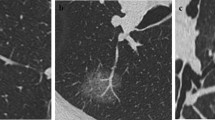

All chest CT examinations included the complete thorax and were performed in the supine position. Scans were obtained during deep inspiration and the patients holding their breath. The CT images were examined and interpreted by two radiologists with more than 5 years of experience in thoracic radiology. The two radiologists independently determined the characteristics of each image, while a third radiologist, with over 20 years of experience in thoracic radiology reassessed the measurements to check for discrepancies. Any discrepancies noted were resolved through discussion among the three radiologists. Central nodules were defined as those located in the bronchi, lobular bronchi, or segmental bronchi of the lungs, while peripheral nodules were defined as those located below the tertiary bronchi. Spiculation was defined as diffusion from the nodule edge into the lungs without contact with the pleural surface. Further, cavitation was defined as the presence of spaces filled with gas and considered regions of transparency or low attenuation. Pleural adhesion was defined as the linear attenuation of pleura or fissures from the nodule. Patterns in CT images, including delamination, central nodule, diffusion, or a popcorn pattern, were considered signs of calcification. A pulmonary artery passing through the nodule, as observed in the CT images was indicative of vascular penetration. Further, bronchial signs on the CT image showed direct bronchial engagement of the nodule. Lobulation was defined as a wavy or scalloped portion on the surface of a lesion, with strands stretching from the nodal edge to the lung parenchyma. Pleural effusion was defined based on a blunted angle of the rib diaphragm in the CT image. Lymph node enlargement was defined as a > 1-cm long lymph node axis in the CT image.

Previous studies have also demonstrated that the CT features of pulmonary nodules can be used to assess their aggressiveness. These imaging features included lobulation, spiculation, bronchus signs, cavitation signs, pleural adhesion signs, and nodule shape [24, 25, 27, 40,41,42,43,44,45,46,47,48,49,50,51,52]. Furuya et al. reported that 82% of lobulated nodules and 97% of acinar nodules are malignant [53]. Lobulation and spiculation of pGGN are also more common in invasive lesions than in pre-infiltrative lesions [18]. Further, Lee et al. found that lobulation is more common in IAC than in pre-infiltrative lesions [42]. However, lobulation was not included as a risk factor for malignant lung nodules in the Herder model [51]. In this study, we identified lobulation as a risk factor for the occurrence of IAC in pGGN; however, no significant differences were observed in this regard with respect to spiculation. A possible reason for this observation is the limited number of nodules with spiculations included in the study. The bronchus signs observed in this study constituted another CT feature that showed association with malignancy. Bronchial signs were more frequently observed in patients with malignant GGN than in those with benign GGN. Reportedly, patients with IAC present with bronchial signs more frequently than those with AIS [45, 54]. Thus, based on our results, bronchial signs were identified as significant predictors of IAC (P = 0.009).